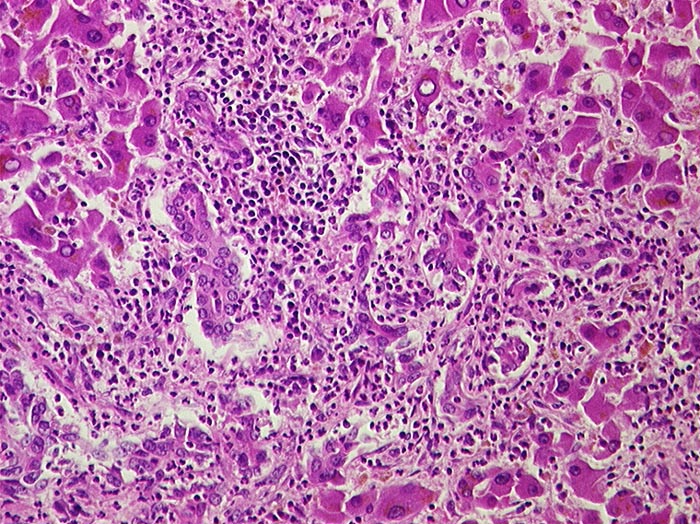

PathoPic ID 888 - Eitrige Cholangitis

Eitrige Cholangitis

Entzündung infektiös

Leber

Leber, Gallenwege, Pankreas

Portalfeld in der unteren Bildhälfte mit dichtem granulozytärem Entzündungsinfiltrat, welches auf die Gallengänge übergreift.

Metastasierendes Pankreaskarzinom mit Tumorbefall von Ductus choledochus und cysticus.

Histologie